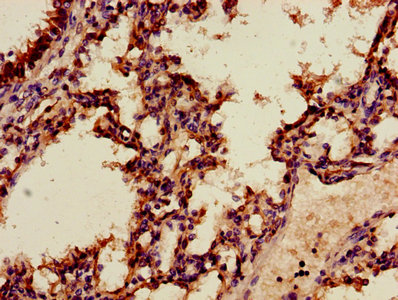

Immunohistochemistry of paraffin-embedded human liver cancer using CSB-PA001840HA01HU at dilution of 1:100

Immunohistochemistry of paraffin-embedded human lung tissue using CSB-PA001840HA01HU at dilution of 1:100